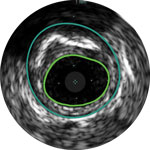

Behandlungsplan Beispiel 2

Lumen mit frischem Thrombus

Mikrokalzifizierung

Kalzifizierte Plaque mit Schallschatten

Gefäßgröße: 6 mm Durchmesser Plaquemorphologie: gemischte, thrombotische Plaque mit mittlerem Calcium Plaquegeometrie: exzentrische Läsion Position des Führungsdrahtes: wahres Lumen

Quick-Cross-Katheter: souverän komplexe Morphologien durchqueren Turbo-Power-Laser-Atherektomie: vorwärts gerichtetes, direktionales Abtragen zur Beseitigung von Thromben; Rotation für verbessertes Abtragen in kalzifizierten Läsionen AngioSculpt Scoring-Ballonkatheter: sicheres Aufweiten von Reststenosen4 Stellarex DCB: entwickelt für hohe Leistungsfähigkeit bei Kalfizifierungen